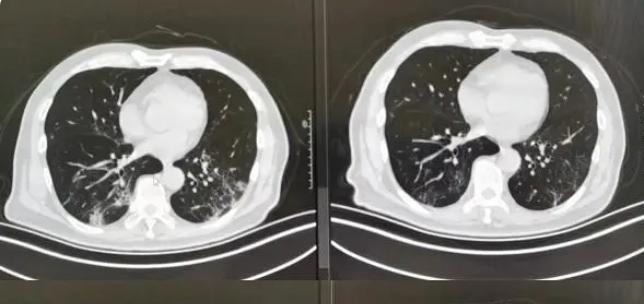

經(jīng)過了疫情的一波沖擊,大部分人都經(jīng)歷了一次新冠病毒的感染,陽康之后很多人都選擇拍胸部CT查看自己的身體情況,當(dāng)人們?cè)诳吹阶约旱臋z查單上寫著”肺部纖維灶“后嚇了一跳,大部分人詢問的問題都是”自己的肺部是不是纖維化了“、“肺部有玻璃陰影要緊嗎”?

對(duì)于人們最關(guān)注的這些問題,上海市胸科醫(yī)院呼吸與重癥醫(yī)學(xué)科副主任李峰表示,不必過度緊張,大部分人都只是出現(xiàn)了感染后的肺間質(zhì)異常,本身是沒有特別的其他癥狀,就像是一個(gè)傷痕,之后會(huì)慢慢恢復(fù)的,無需過多擔(dān)心,李峰表示,當(dāng)人在眼眶后檢查胸部CT,的確會(huì)發(fā)現(xiàn)肺部會(huì)有一些磨玻璃影,磨玻璃小結(jié)節(jié)等情況,這都是由于感染病毒之后才出現(xiàn)的,一般情況下不會(huì)再擴(kuò)大,而且過一段時(shí)間就會(huì)慢慢康復(fù)。

對(duì)于之前感染新冠病毒之后出現(xiàn)了肺部感染的人群建議等康復(fù)之后觀察隨訪,等到三個(gè)月到6個(gè)月左右,復(fù)查CT,如果沒有其他不適的癥狀,可以等到陽康之后3~6個(gè)月左右再檢查胸部CT,李峰解釋道,對(duì)于輕癥的肺炎患者,做檢查顯示肺部有纖維條縮影的情況無需特殊的干預(yù)。

專家表示,正常情況下,肺部出現(xiàn)纖維灶并不代表一定是壞的,這就像是人身體某個(gè)部位被劃傷之后留下的一個(gè)傷疤,不用特殊治療,也不用吃藥,肺纖維化分為兩種,一種是指特發(fā)性肺纖維化,第2種是繼發(fā)性纖維化,人們感染新冠后出現(xiàn)的屬于繼發(fā)性肺纖維化,重重就輕的,甚至充不上肺纖維化,所以無需過度擔(dān)心。